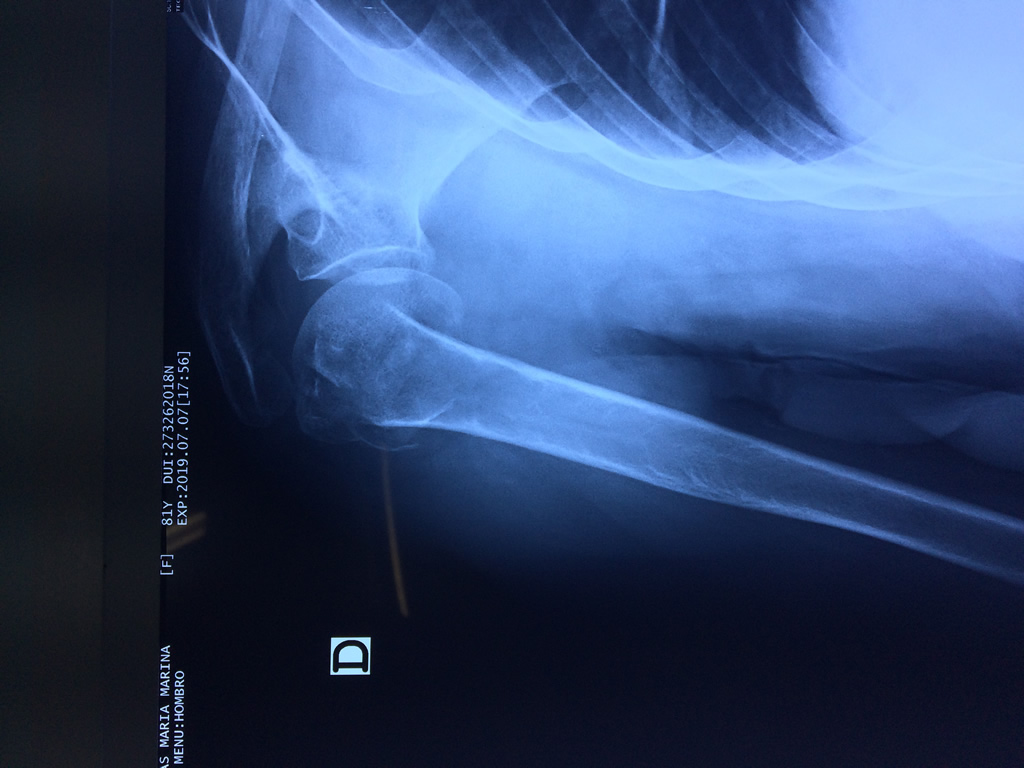

La principal articulación del hombro es la que une la cabeza del húmero con la escápula, recibe el nombre de articulación escapulohumeral y presenta dos superficies articulares, una de ellas corresponde a la cabeza del humero que tiene forma semiesférica y la otra es la cavidad glenoidea de la escápula, estas superficies están recubiertos por cartílago que permiten un movimiento suave e indoloro.